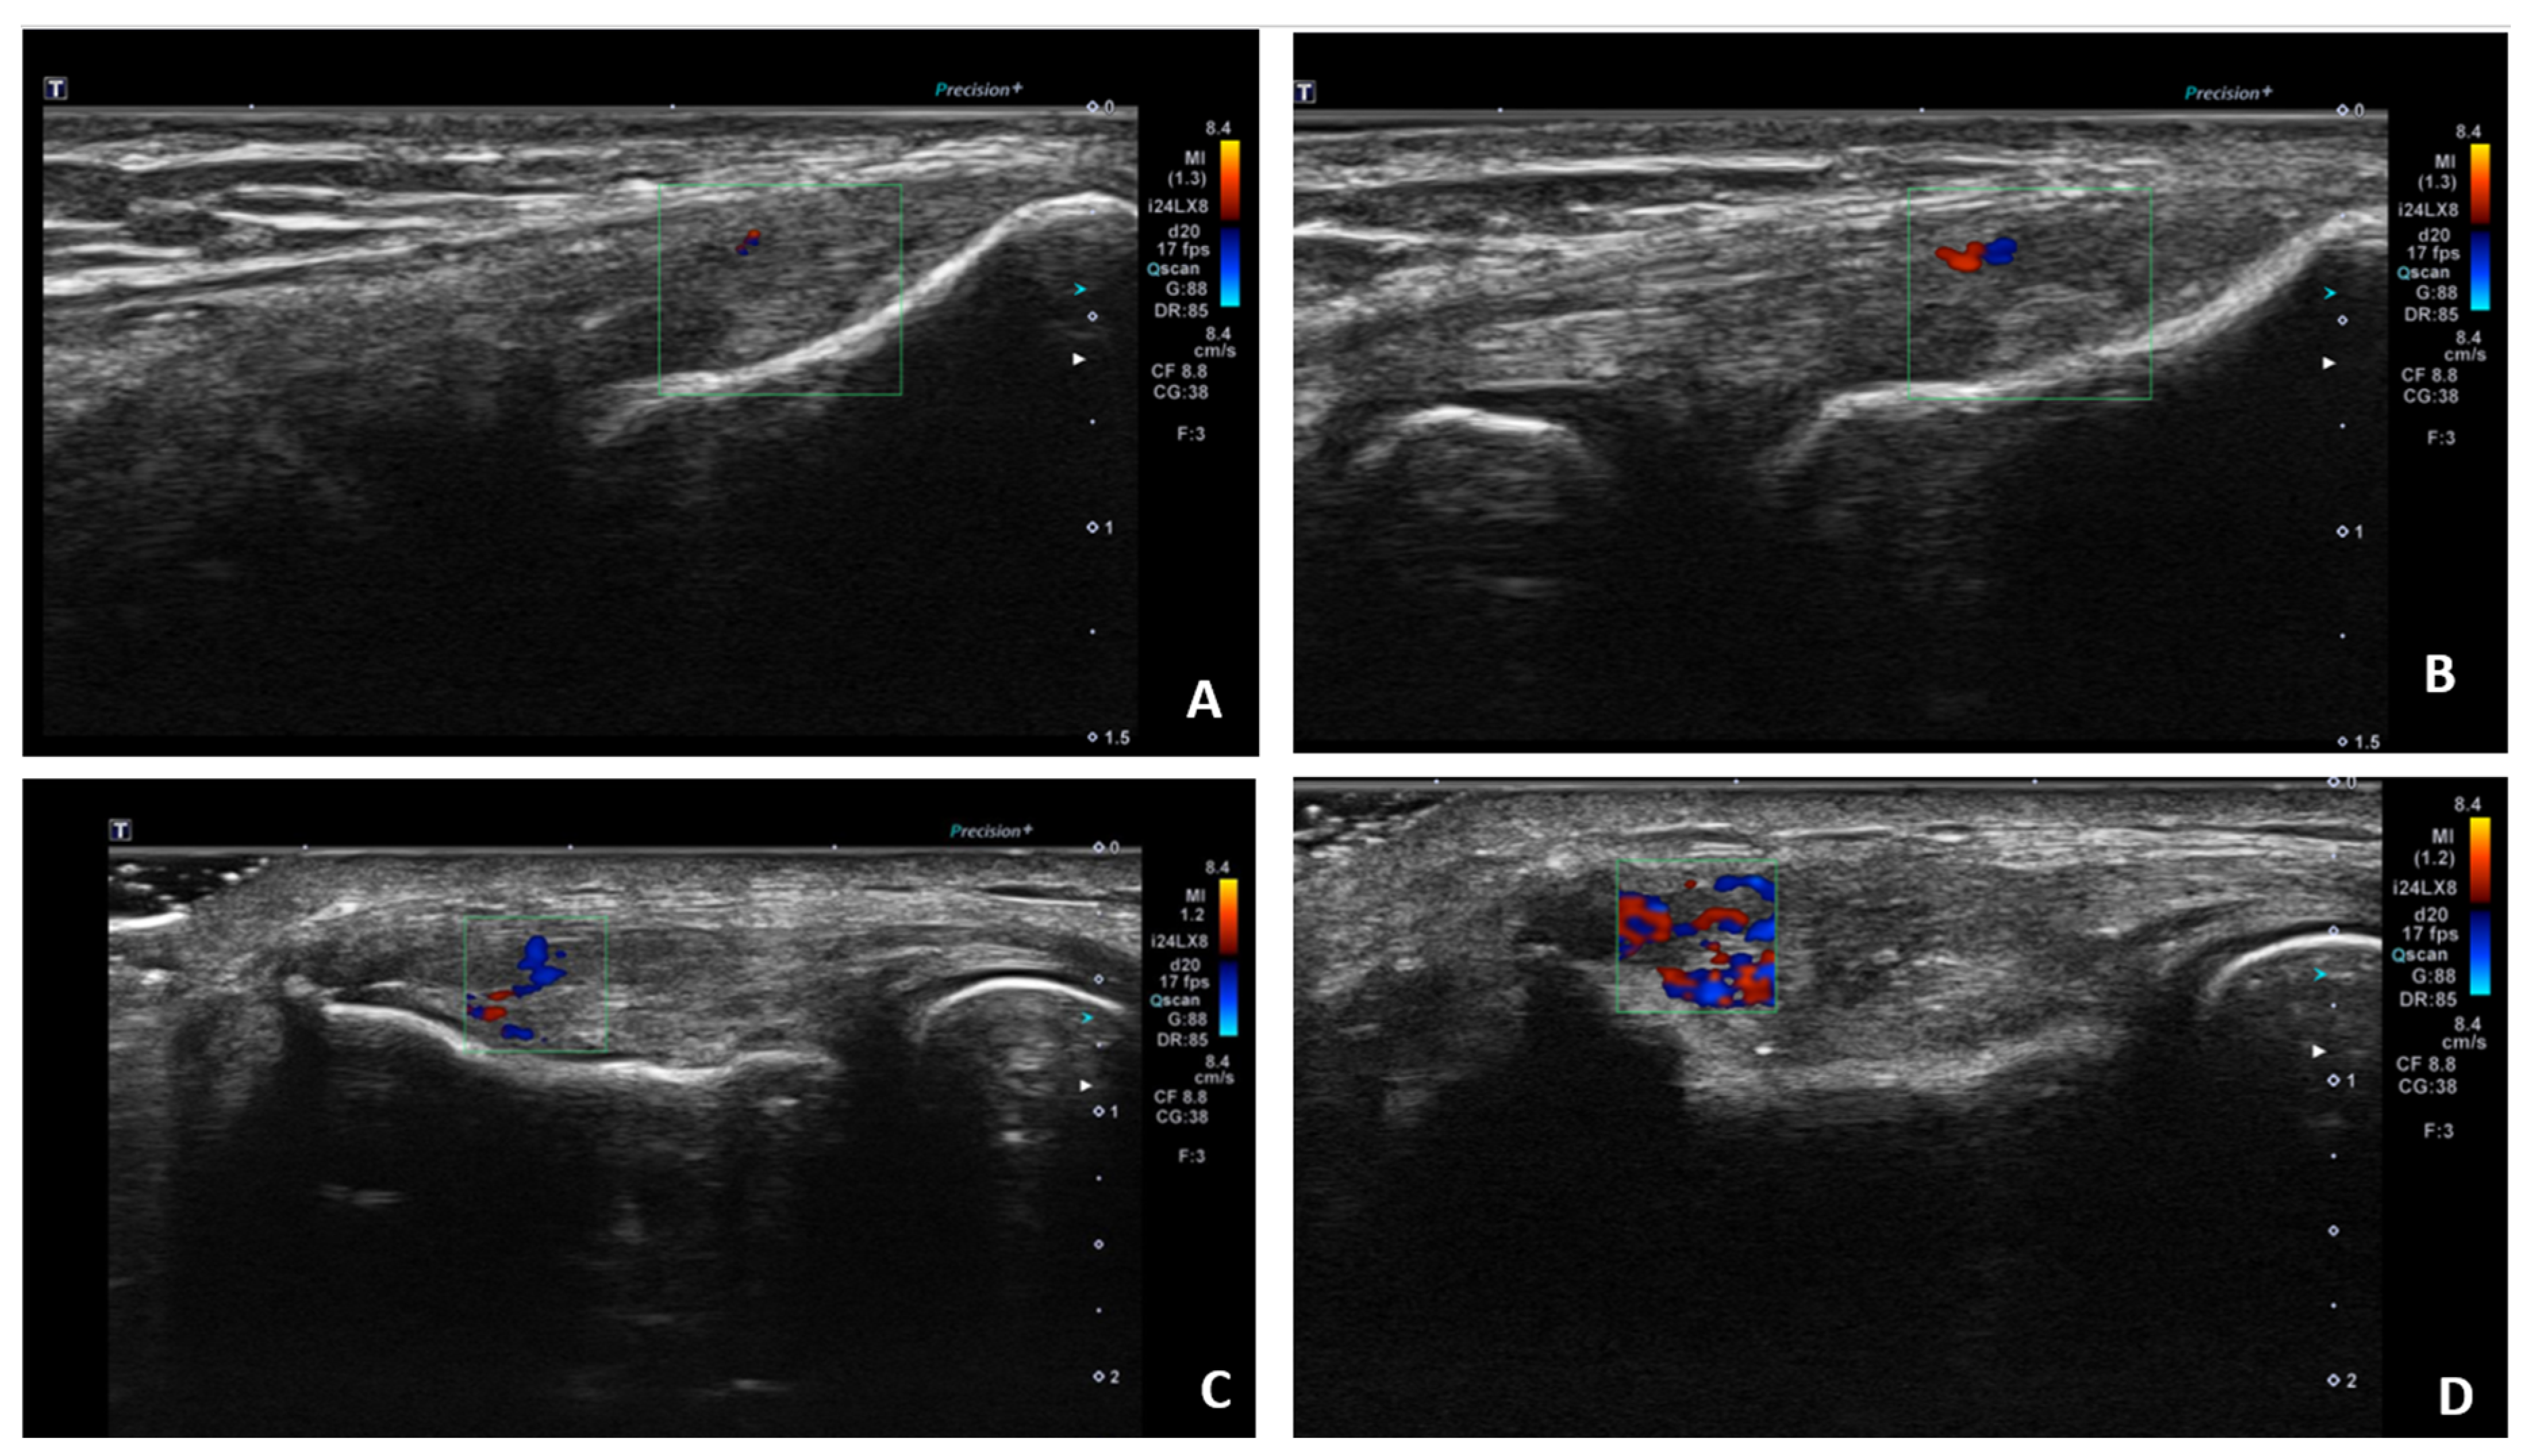

| US-vascularity at baseline | 2.2 | 1.43 | 1.9 | 1.5 | 2.9 | 1.1 | 0.09 |

| SMI at baseline | 9.8 | 9.3 | 9.3 | 7.5 | 12.4 | 6.9 | 0.6 |

| US-vascularity after treatment | 2.1 | 1.4 | 1.7 | 1.4 | 1.4 | 1.1 | 0.3 |

| SMI after treatment | 9.8 | 7.8 | 10.2 | 8.4 | 7.06 | 6.6 | 0.2 |